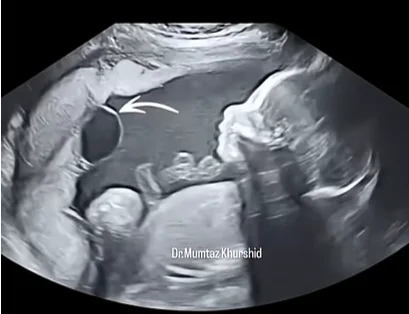

Dây rốn thắt nút (True Umbilical Cord Knot)